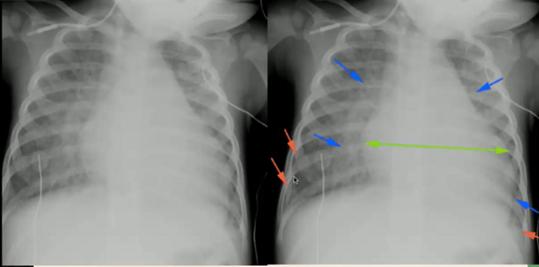

图20.心源性肺水肿:心影增大(绿)、线状间质阴影(蓝)、胸膜增厚(红,卧位时胸腔积液表现)②气胸、纵隔积气、心包积气鉴别

图21.气胸(左):心缘旁见气胸线;纵隔气胸(中):气胸线延伸到肺下野,可通过纵隔延伸至皮下软组织,颈部、胸前多见;心包积气(右):积气限制在心包区域

图22.仰卧位气胸(左):深沟征(大片肺野透亮,纹理消失;肋膈角较对侧深);仰卧位纵隔气胸(右):天使翅膀征(胸腺边界特别清晰,可有“漂浮感”)③下呼吸道异物